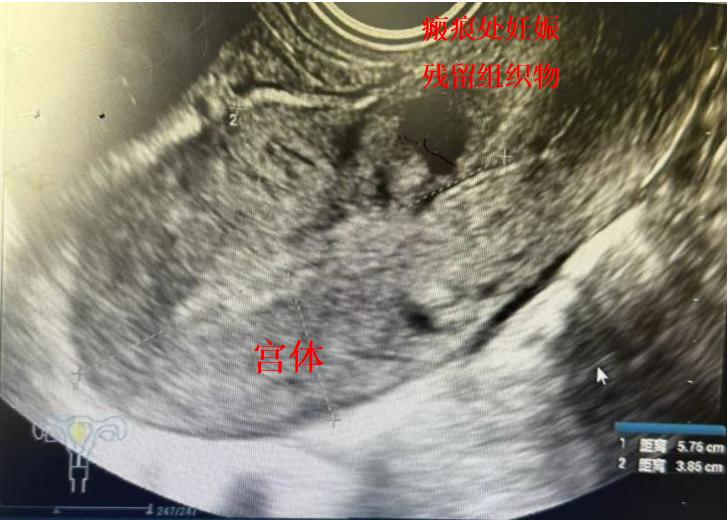

▲患者影像显示

检查中发现苏女士的子宫上存在一个高风险病灶——剖宫产瘢痕部位妊娠组织残留。追问病史得知,患者曾于2013年、2018年各接受过一次剖宫产术,并于今年5月5日因自然流产出血在外院行清宫术。随后的检查证实了这一隐患:三维彩超提示子宫下段切口区见约34×21mm的异常回声团,考虑妊娠组织残留伴浅肌层植入可能;盆腔MRI进一步显示瘢痕处存在约32×14×17mm的异常信号影,病灶与子宫前壁分界不清,且凸向浆膜层,符合III型剖宫产瘢痕妊娠(外生型)诊断。这种情况如同子宫上的一颗“定时炸弹”,病灶血供丰富且位置凶险,随时可能引发难以控制的大出血,严重威胁患者生命。